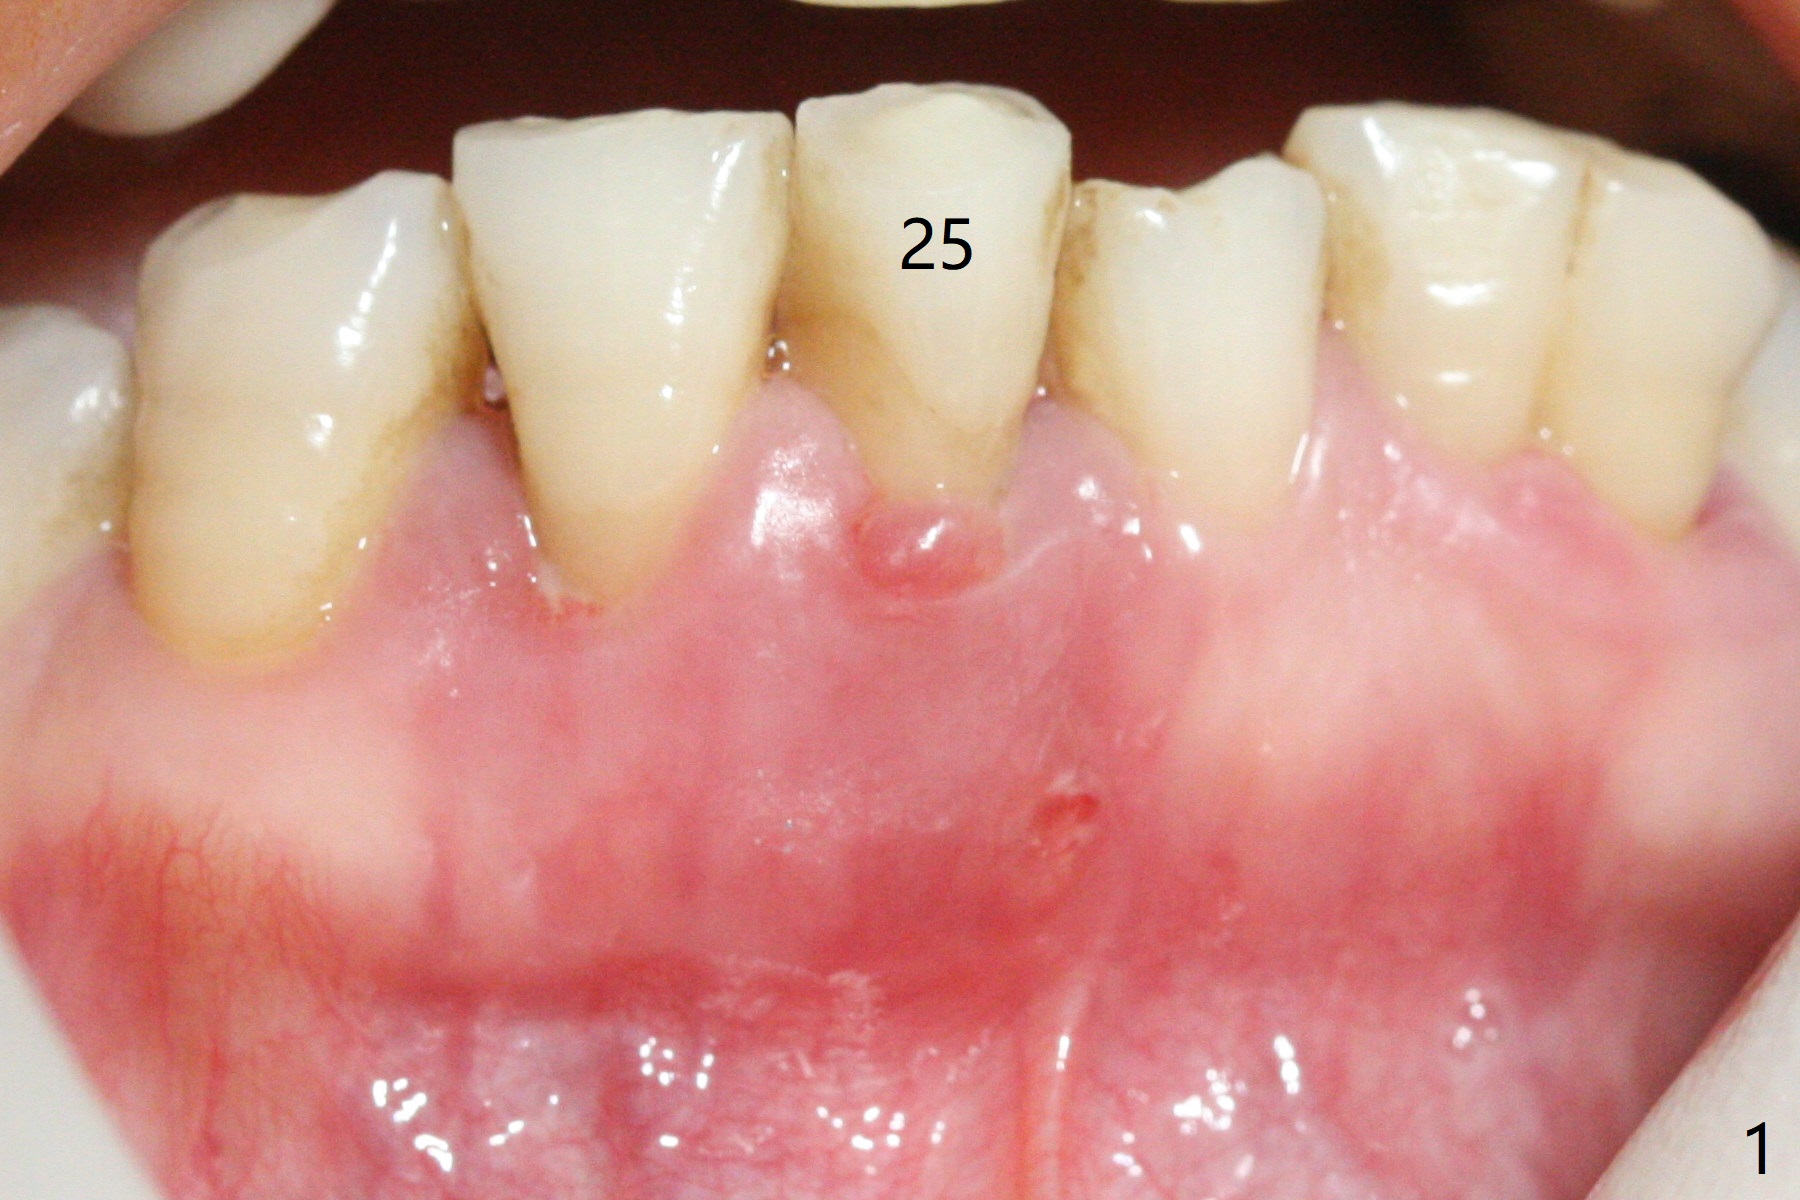

There is gingival inflammation at #25 buccally (Fig.1) and lingually (Fig.2). The bone loss is severe (Fig.3). Soft and hard tissue heights are 5 mm (cuff will be 4 mm) and 10 mm (implant will be 12 mm with 2 mm outside the native bone, Fig.4). The apex of the affected tooth appears deviated distal (Fig.5 *). The initial osteotomy happens to follow the long axis of the socket (Fig.6); to establish a correct trajectory, a new osteotomy should be made at the site labeled as a red line. In fact it is executed as planned (Fig.7). Because of the narrow flat ridge buccolingually, a 2.5x12(4) mm 1-piece implant is placed with >40 Ncm (Fig.8). With deeper placement of the implant, Vanilla graft is placed in 2 steps (Fig.9,10). The patient will return 2.5 months for extraction and implant of the fused teeth #22 and 23. No implant threads are exposed 10 months postop (Fig.11). CT taken 11 months postop shows that the 2.5 mm implant is in the middle of the bone (Fig.12) or 2 years post cementation (Fig.13).